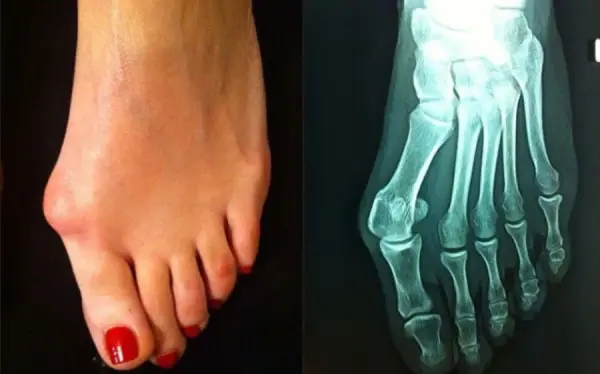

Κότσι: Γιατί δημιουργείται, πώς αντιμετωπίζεται